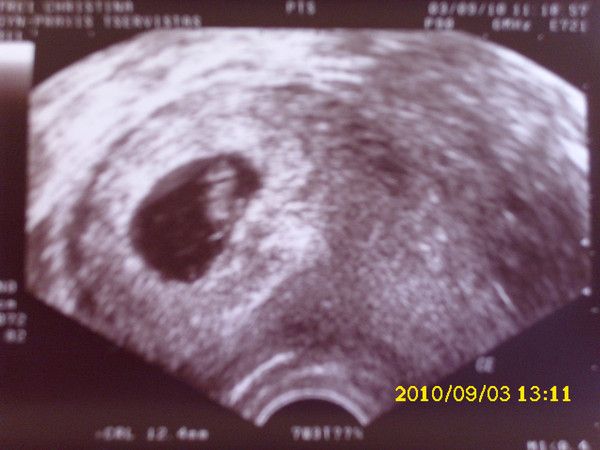

Tinchen´s Krümelchen 8.+2 SSW (9. SSW)

03.09.2010

Der Krümel ist jetzt 12,4mm groß und das kleine Herz ist auch fleißig am schlagen!!